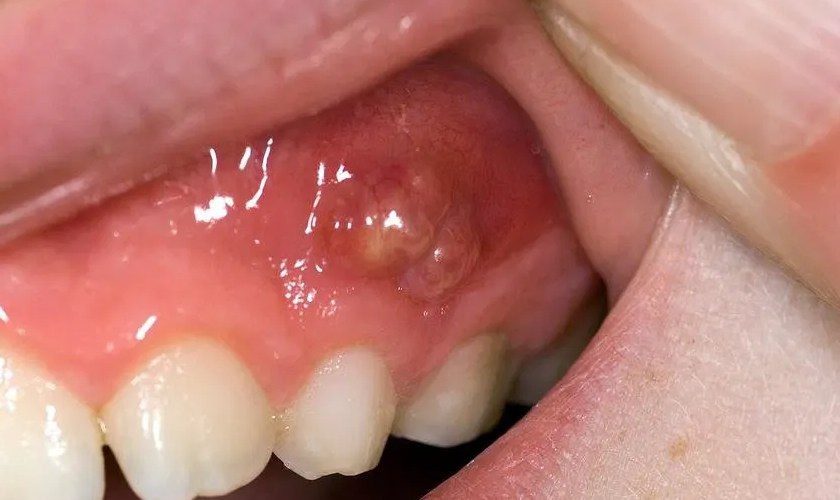

Một điểm đặc trưng của áp xe nha chu là mủ bị “kẹt” trong túi nha chu, không thoát ra ngoài. Áp lực nội mô tăng lên làm người bệnh đau dữ dội, cảm giác như răng bị đội lên hoặc cộm khi cắn. Đây là giai đoạn cấp tính cần xử trí nhanh vì mủ càng tích tụ, mô quanh răng càng bị phá hủy. Do đó, điều trị áp xe quanh răng cấp không thể trì hoãn.

Điểm quan trọng trong lâm sàng là nhận diện đúng áp xe để điều trị sớm. Áp xe quanh răng cấp thường gây đau dữ dội, sưng khu trú vùng nướu, có thể xuất hiện mủ hoặc hơi thở hôi. Răng đau khi gõ hoặc khi cắn, đôi khi có cảm giác răng “dài ra” do mô quanh răng phù nề. Đây là khác biệt so với đau răng do nhạy cảm đơn thuần.

Bước quan trọng nhất trong điều trị áp xe cấp là dẫn lưu mủ áp xe. Khi mủ được thoát ra, áp lực trong mô giảm nhanh, người bệnh sẽ thấy giảm đau rõ rệt. Dẫn lưu có thể thực hiện qua túi nha chu hoặc rạch dẫn lưu tùy mức độ sưng. Đây là bước mang tính “giải áp” và là nền tảng để các phương pháp khác phát huy hiệu quả.